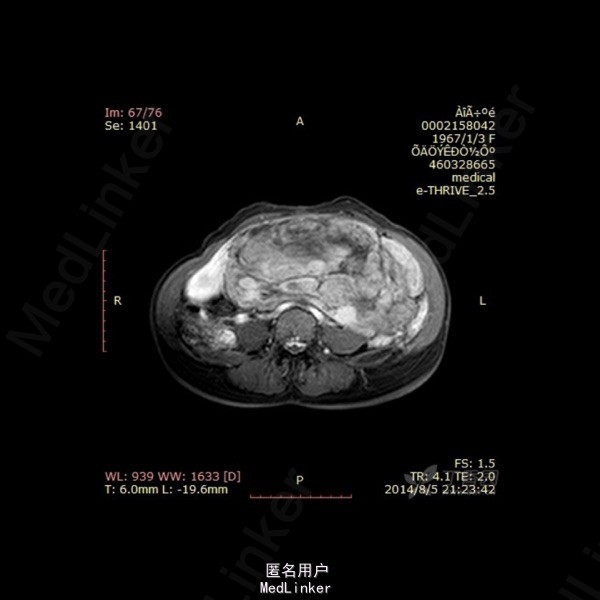

影像表现:左侧附件区示一巨大的病变,呈长T1长T2异常信号影,期内多发分隔,增强后呈不均匀强化,强化较明显。DWI示低信号。总的来看,病变为一个巨大肿块,内有分隔,境界较清。 诊断:我认为首选左侧阔韧带子宫肌瘤可能性大。由于其短期内增大,不除外瘤内出血的可能。 转于:丁香园